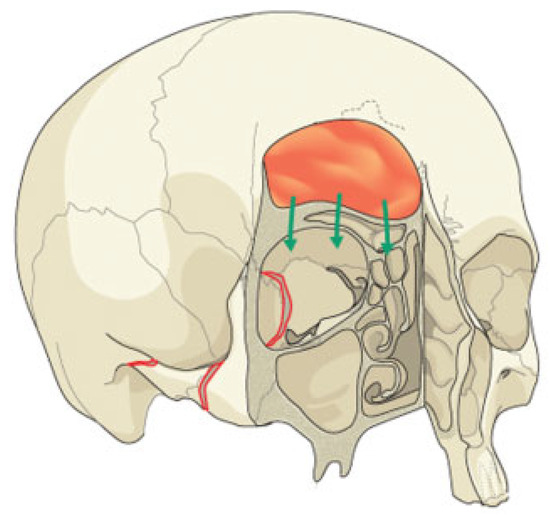

Figure 2. Maxillary sinus development. The progressive increase in size of the maxillary sinus (green) is seen (A) at birth, (B) at 5 years of age, and (C) in the adult.

In utero, the sinuses and nasal cavity are a single structure. The ethmoid, frontal, and maxillary sinuses then subdivide from the nasal cavity in the second trimester. Subsequent sinus formation occurs in a predictable sequence. The maxillary sinuses are the first to develop. The growth of these paired sinuses is biphasic, occurring between 0 to 3 and 7 to 12 years of age. During mixed dentition, the cuspid teeth are immediately beneath the orbit: hence the term eye tooth in dental parlance. It is not until age 12 that the maxillary sinus expands, in concert with eruption of the permanent dentition. At 16 years of age, the maxillary sinus reaches adult size (Figure 2) [1]. These changes are a quintessential example of the how ongoing sinus development impacts fracture patterns and susceptibility. Specifically, the presence of the unerupted maxillary dentition serves to resist orbital floor fracture in young children [2].